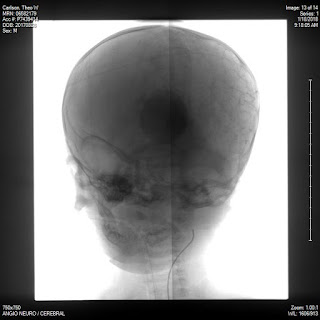

Theo's Angiogram

At the request of our Neurosurgeon, Dr. Klopfenstein, Theo had an angiogram today. An angiogram is "an x-ray test that uses a special dye and camera to take pictures of the blood flow in an artery or a vein" (WebMD). The angiogram was done by our Interventional Radiologist, Dr. Fraser. The doctor enters a vein in the leg, close to the groin, and then follows that vein up through the body, passing through the heart, and into the brain.

He then explained to us what they found and what his thoughts were. Dr. Fraser told us that he believes he can fix Theo's aneurysm with one surgery. The surgery would be very similar to what they did today. They would enter the vein in his leg, go up into the brain, and insert coils into the aneurysm. This will cause the blood flow to return to it's normal amount and pressure. After the procedure is done Theo will be in the hospital for 3-5 days while they monitor him for heart failure, hemorrhage, and other complications. He will need to have regular checkups (probably for the rest of his life) to make sure that the coil is doing what it's supposed to do and that his heart is fine. Dr. Fraser also told us that the neurosurgeon will also be preforming surgery on Theo to fix his hydrocephalus. This surgery is more invasive and involves the neurosurgeon

Dr. Fraser then explained why Theo's angiogram took so long. They punctured the vein in his left leg first but the vein didn't look strong enough so they had to puncture his right side. He has a little puncture on his left side and a larger one on his right which they had to stitch up.

Angiogram pictures: